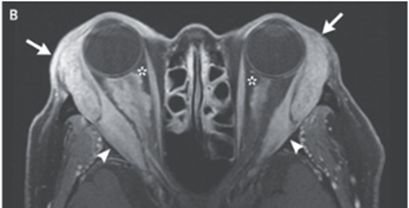

MRI施行され、両側涙腺と外側直筋の腫脹が示唆された。また視神経の周囲には腫瘤性病変を認めた。